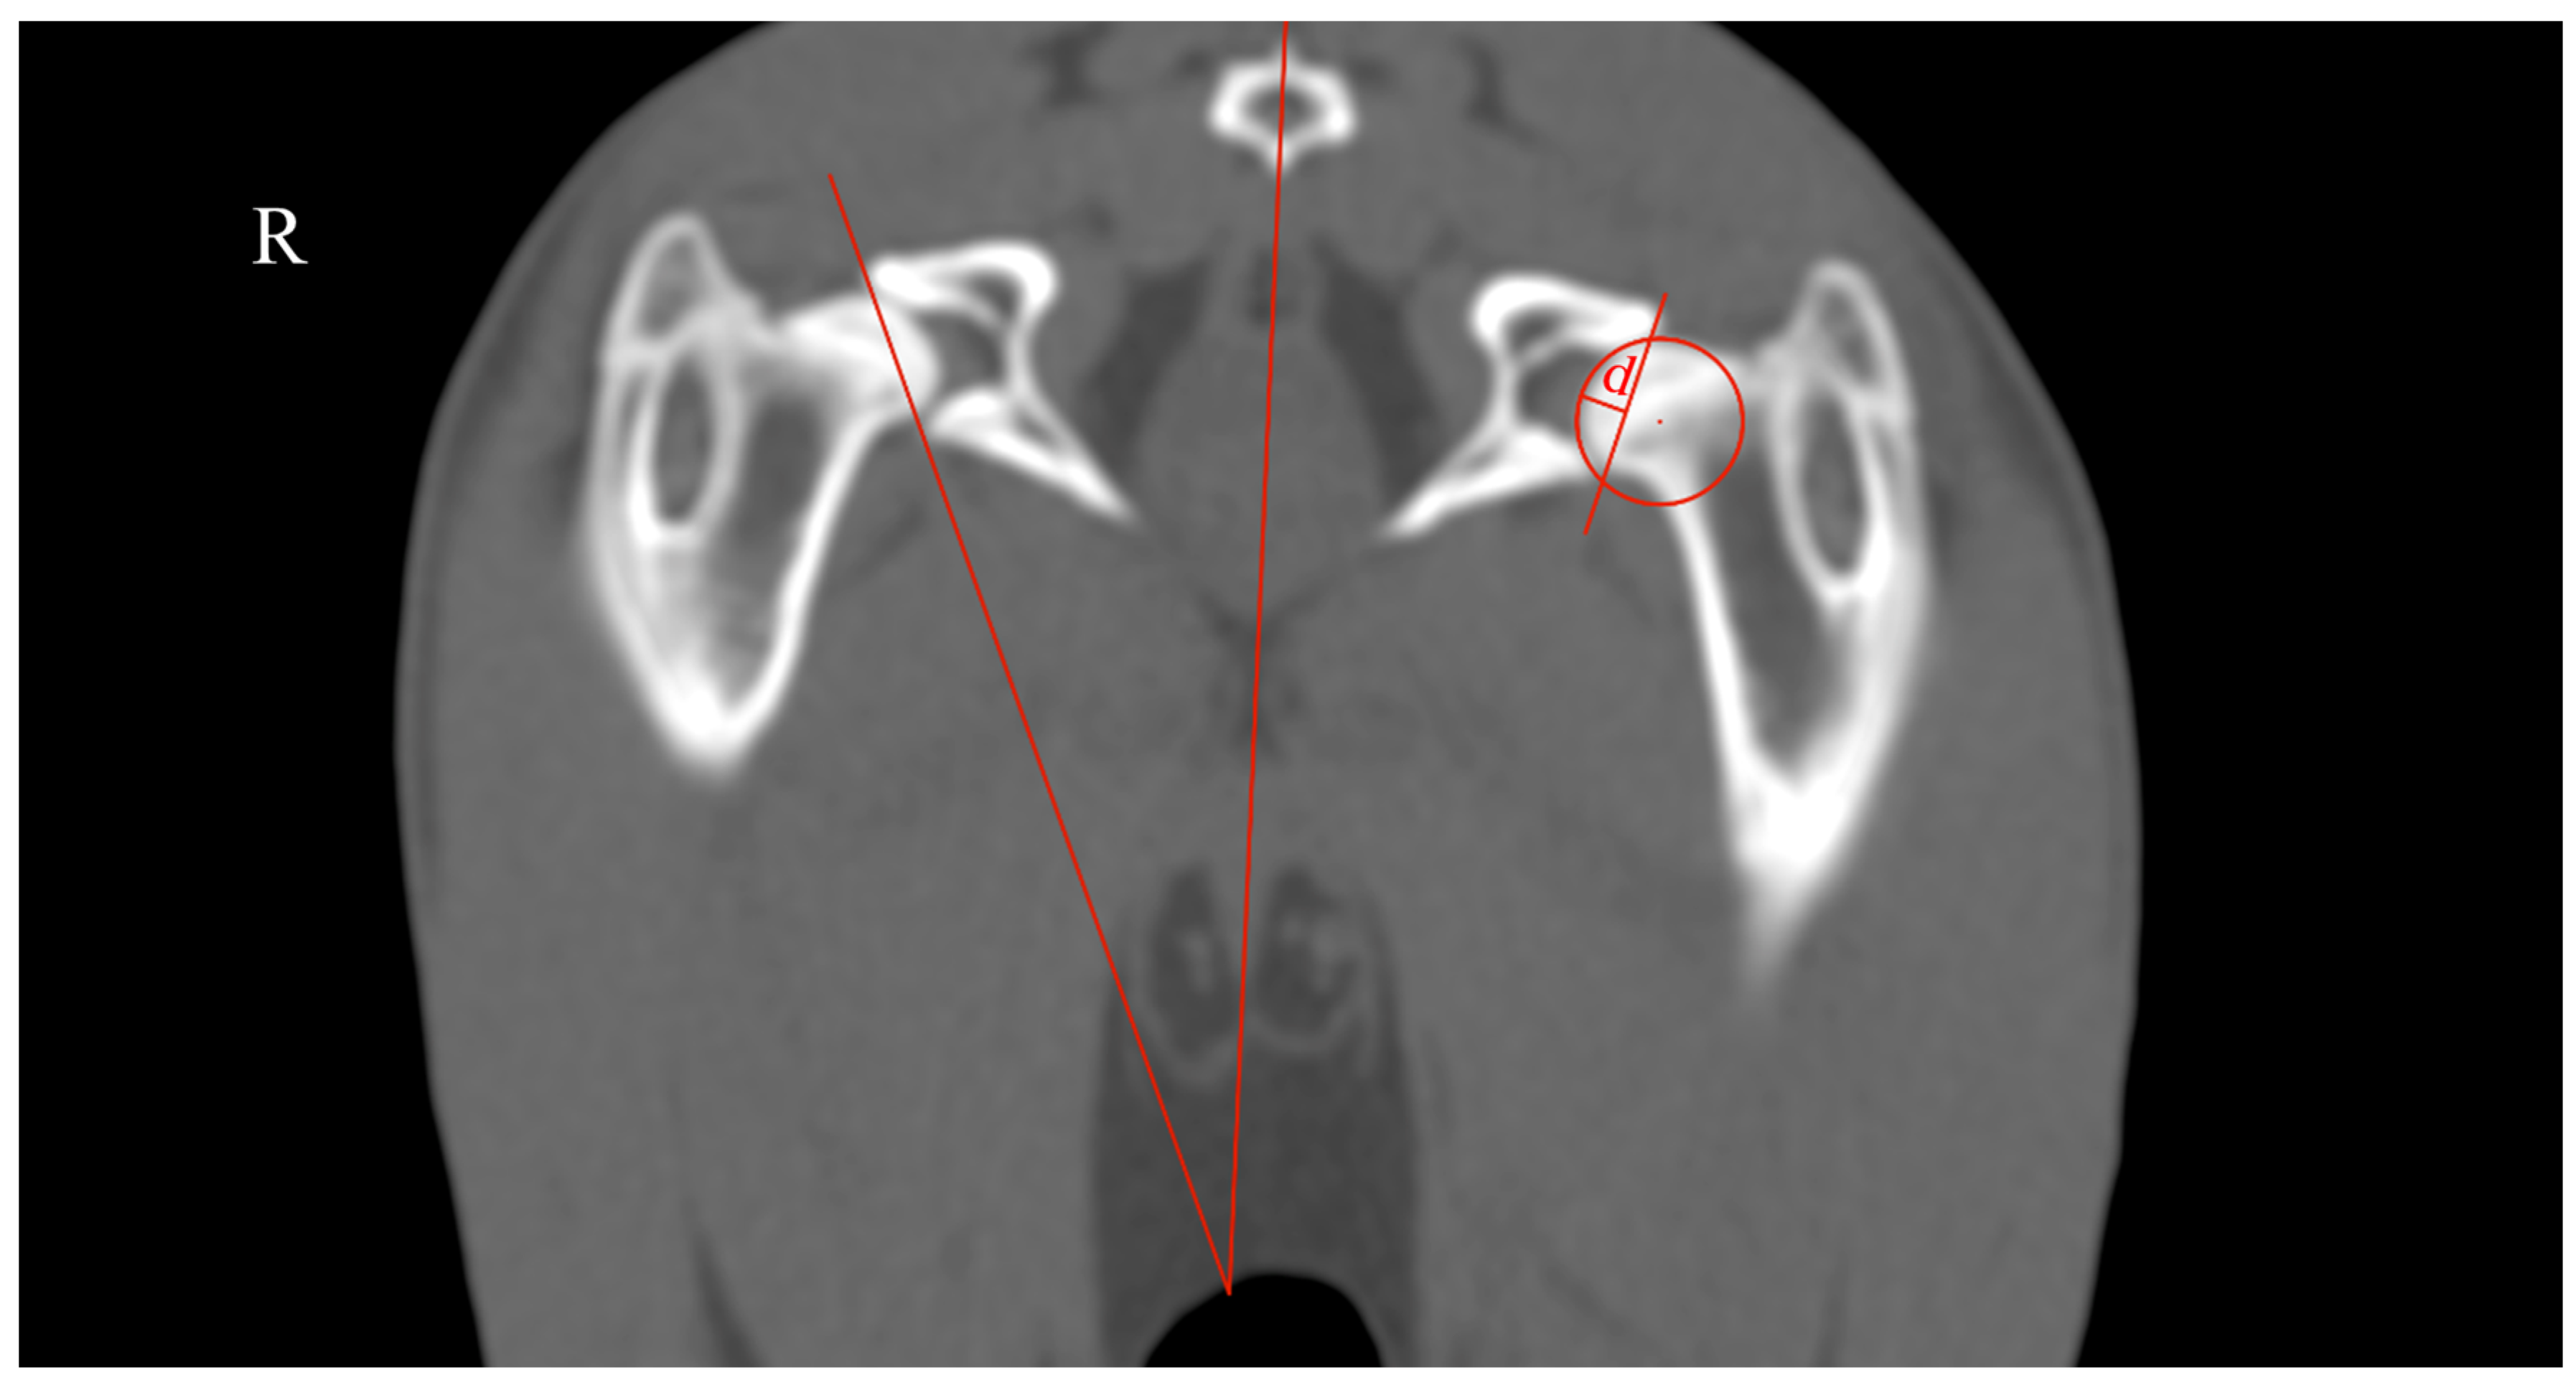

The rabbits were submitted to a computed tomography (CT) assessment (Revolution™ ACT-16 slices, General Electric Medical Systems, Buckinghamshire, UK) and were positioned in sternal recumbency in a knee weight-bearing position in a hole of foam sponge. It was defined as a field-of-view that covered the entire hip joint and femur, and the images were acquired in the helical mode using a thickness of 1.25 mm and bone algorithm reconstruction (WL 400, WW 2000). The measurements performed were the ADi_TC and AV (Figure 4).

ADi_CT was measured as the ratio between ‘d’, the acetabular depth, and the acetabular diameter (d/Ø, in mm). Distance ‘d’ was defined as the biggest perpendicular distance to the line tangent to the dorsal and ventral acetabular edges [12]. The AV was measured as the angle between the line that intersected the center of the coccygeal vertebrae body and the middle of the pubic symphysis and another line tangent to the most lateral edges of the dorsal and ventral acetabular rim [13].

Figure 4. Transverse CT scan of the hip joint illustrating the methodology used to evaluate the acetabular depth index (ADi_CT) and the acetabular ventroversion (AV). R: right side. ADi_CT (left side) was measured as the ratio between ‘d’, the acetabular depth, and the acetabular diameter. Distance ‘d’ was defined as the biggest perpendicular distance to the line tangent to the dorsal and ventral acetabular edges. The AV (right side) was measured as the angle between the line that intersected the center of the coccygeal vertebrae body and the middle of the pubic symphysis and another line tangent to the most lateral edges of the dorsal and ventral acetabular rim.